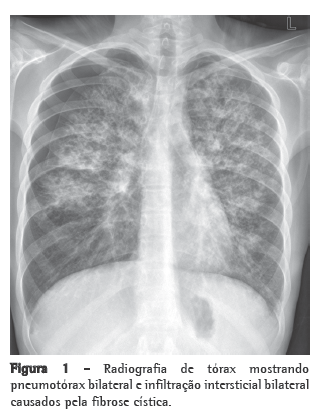

A radiografia de tórax evidenciou abaulamento de arco médio; a tomografia de tórax evidenciou dilatação de ramos arteriais, com relação artéria: brônquio > 1, espessamento septal e micronódulos difusos (Figura 1). A avaliação funcional pulmonar não mostrou alteração de volumes ou fluxos pulmonares, mas evidenciou redução significativa da capacidade de difusão (30% do previsto). Ao ecocardiograma, constatou-se aumento de câmaras direitas e pressão sistólica de artéria pulmonar estimada em 84 mmHg. No teste de caminhada de seis minutos (TC6), a distância percorrida foi de 375 m. As investigações para doenças do tecido conectivo, AIDS, hipertensão portal e embolia pulmonar crônica tiveram resultados negativos.

Mais especificamente, os achados característicos na tomografia de tórax incluem espessamento septal liso, micronódulos difusos e opacidades em vidro fosco.(8) As provas de função pulmonar caracteristicamente mostram redução da capacidade de difusão.(5)